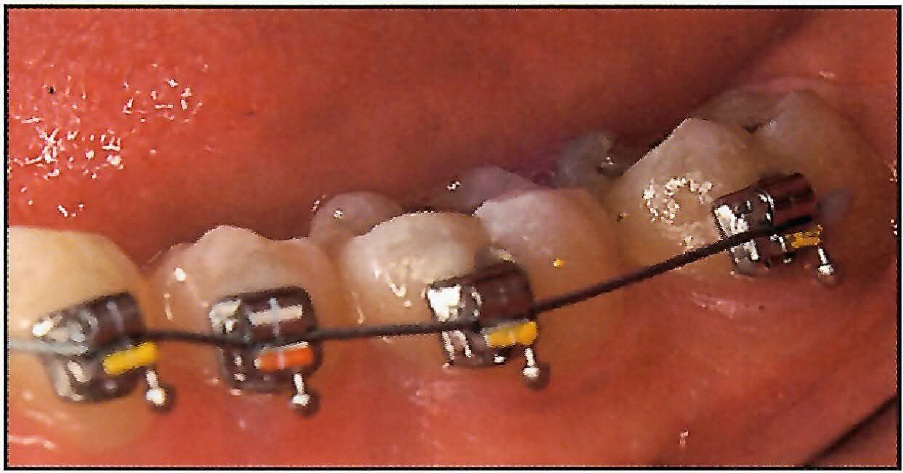

This 12-year-old male patient had severe bimaxillary crowding that necessitated four bicuspid extractions. The mandibular arch had a buccally displaced cuspid and a rotated and slightly lingually displaced lateral incisor (Fig. 7A). Figures 7B-E illustrate the alignment achieved in each arch with only nine weeks of treatment using single .016" Supercable archwires. The panoramic and periapical radiographs showed no root blunting after this remarkable amount of tooth movement (Fig. 7F-H). The patient reported no pain or discomfort.

Fig. 7 12-year-old male with severe bimaxillary crowding and four first bicuspid extractions. A. Initial engagement of mandibular .01611 Supercable. B. Two weeks later, showing initial incisal and cuspid alignment. Note 2mm of excess wire distal to terminal molar bracket. C. Seven weeks later, showing absence of incisor flaring. Note 10mm of archwire distal to molar bracket attachment after closure of extraction spaces. D. Initial engagement of maxillary .01611 Supercable. E. Incisor alignment nine weeks later. Note distal movement of cuspids and closure of extraction spaces without any mesial migration of posterior teeth (continued in next image).